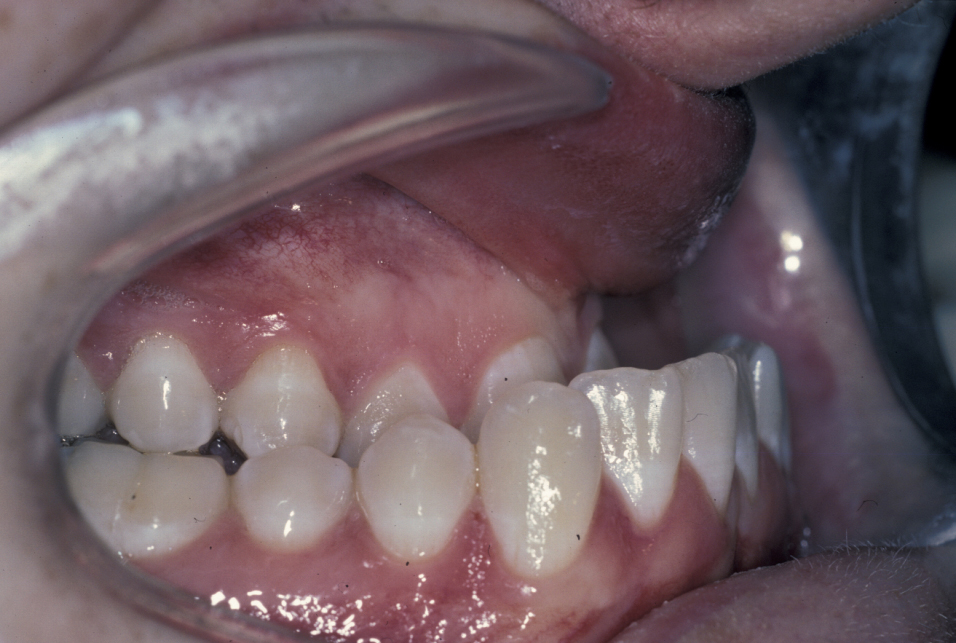

The molar and incisal relationships are examined visually and are formally documented by photographs (see Figure 5, Figure 6 and Figure 7 for examples) and study models (see below).

Figure 5: Intraoral view showing a class III malocclusion (underbite).

Figure 6: Intraoral view showing a class III malocclusion (underbite).

Figure 7: Intraoral view of a class III malocclusion (underbite).